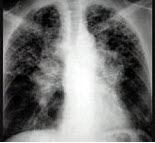

女,17岁,背部和正中胸部急性疼痛和带状疱疹感染,结合图像,最可能的诊断是()

A.镰状细胞贫血

B.地中海贫血

C.系统性红斑狼疮

D.类风湿关节炎

E.白血病